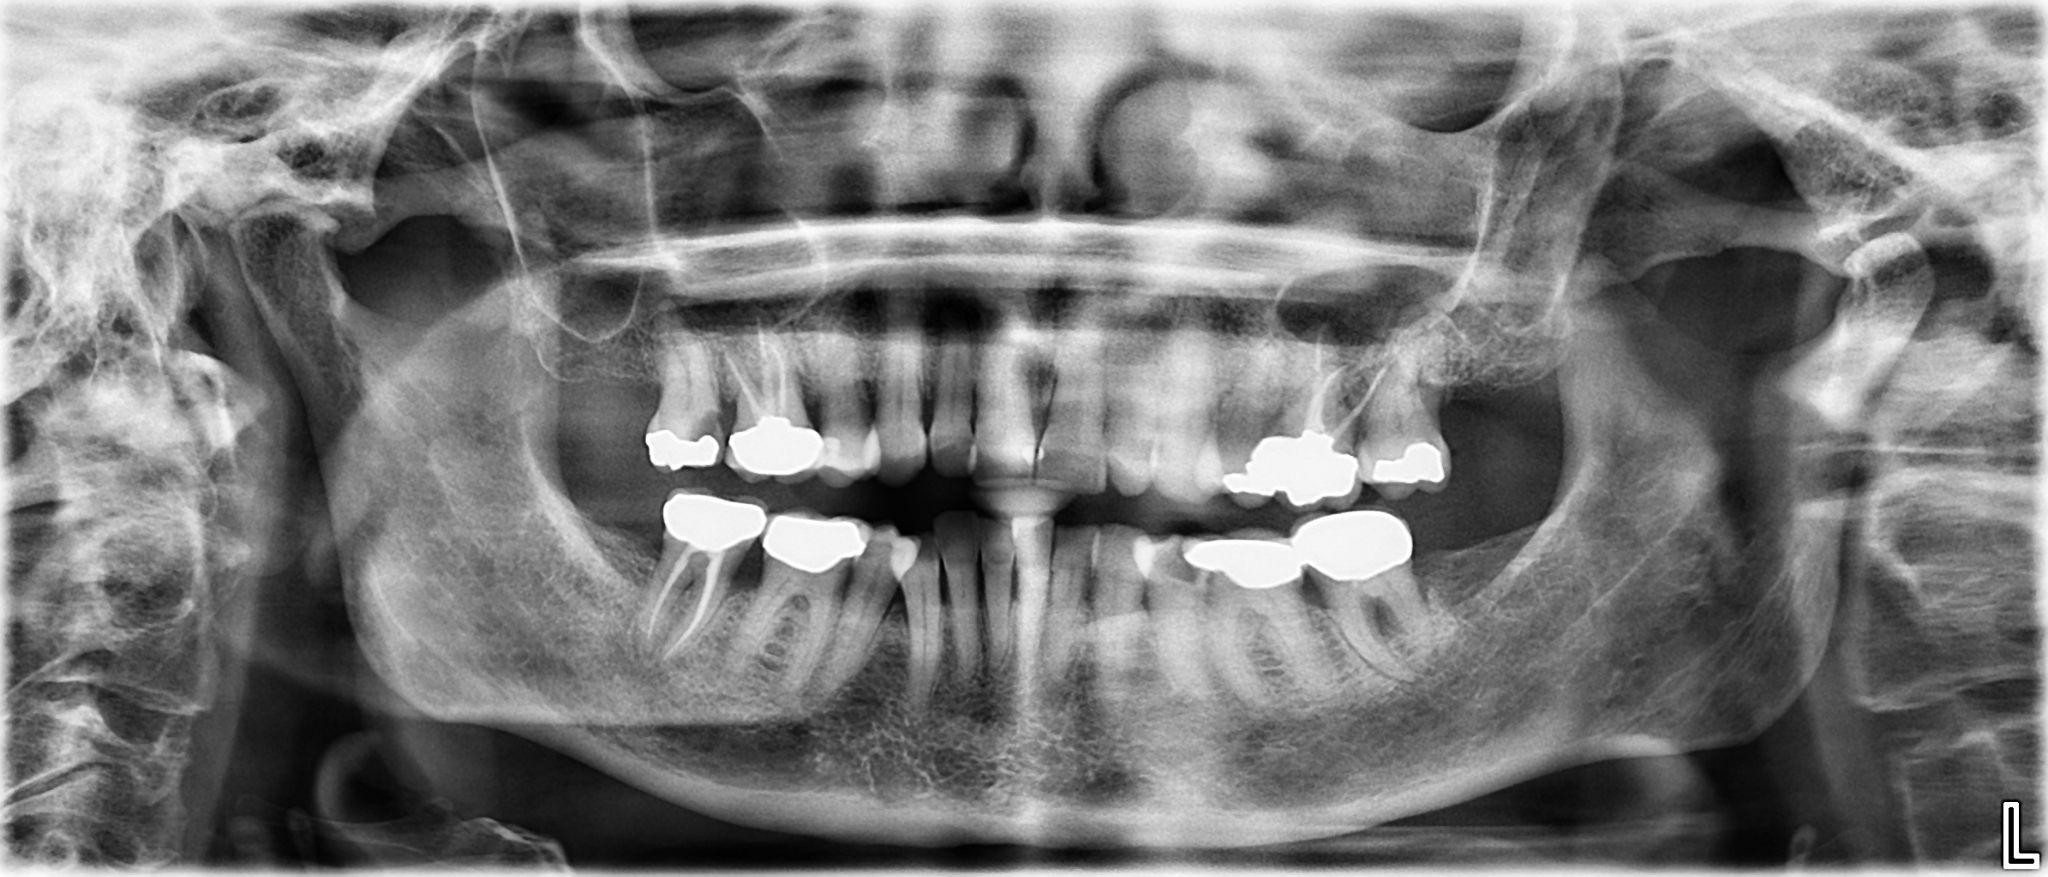

14. What option cannot be selected for the upper jaw of this panoramic X ray?

15 / 25

15. What option cannot be selected for the lower jaw of this panoramic X ray?

16 / 25

16. What option cannot be selected for the upper jaw of this panoramic X ray?

17 / 25

17. What option cannot be selected for the lower jaw of this panoramic X ray?

18 / 25

18. What option cannot be selected for the upper jaw of this panoramic X ray?

19 / 25

19. What option cannot be selected for the lower jaw of this panoramic X ray?

20 / 25

20. What option can be selected for the upper jaw of this panoramic X ray?

21 / 25

21. What option cannot be selected for the lower jaw of this panoramic X ray?

22 / 25

22. What option cannot be selected for the upper jaw of this panoramic X ray?

23 / 25

23. What option cannot be selected for the lower jaw of this panoramic X ray?

24 / 25

24. What option cannot be selected for the upper jaw of this panoramic X ray?

25 / 25

25. What option cannot be selected for the lower jaw of this panoramic X ray?